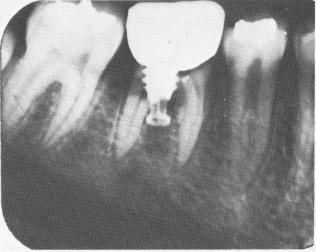

Fig. 8-75. A 4-year postoperative radiograph. Root canal therapy could not be done since the tooth split exactly through the center of the canals. The translucencies seen along both roots are caused by internal resorption.

1 Xray shows lower vent plant implant, tooth has split exactly at center